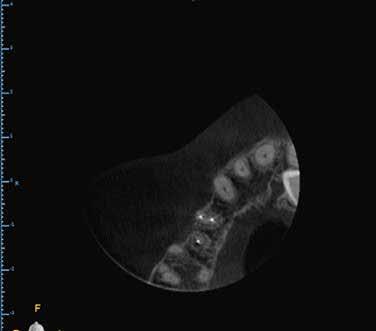

AZ ENDODONCIAI ELLÁTÁS SORÁN TÖRTÉNŐ

DENTINPREZERVÁLÁS LEHETŐSÉGEI

1. a–f ábrák: A cingulumon keresztül gömbfúróval kialakított hozzáférés a trepanációs kavitás labiális irányba történő túlzott mértékű kiterjesztését eredményezheti, és ez lényegesen növelheti a perforáció esélyét (a). A guttapercha átsejlik a lágyrészek alatt (b). Klinikailag igazolt perforáció (c). A preoperatív sagittális irányú CBCT-szeleten jól látható a labiális perforáció (d). Labiális irányú perforáció (fekete nyíl; e). A tényleges gyökércsatorna (piros nyíl; f).

2. a-b ábrák: A cingulumon keresztül gömbfúróval végzett trepanálás túlzott pericervikális dentin áldozattal, fordított tölcsér effektussal és perforációk kialakulásával járhat (fehér nyíl).

5. a–l. ábrák: Az incisális élen keresztül kialakított hozzáférés lehetővé teszi a pericervikális dentin megőrzését. Kalcifikáció esetén CBCT-felvétel készítése hasznosnak bizonyulhat a hozzáférési nyílás tervezése során (a–d) . Minden fog koronai helyreállítása a gyökértömés elkészítésével egyidejűleg történt. A négyéves (e–h) és a kétéves (i–l) kontrollok alkalmával készített röntgenfelvételeken teljes gyógyulás látható. Mindkét fog tünetmentes és funkcióképes volt. (Dr. Viraj Vora esetei)

9. a–j. ábrák: A szuvas lézión és a meglévő restaurátumon keresztül történő mezializált és distalizált hozzáférés (a–f). A fogak restaurálása közvetlenül a gyökértömések elkészítése után történt. Az egyéves kontroll során készített röntgenfelvételen a gyógyulás jelei láthatóak, annak ellenére, hogy a gyökércsatornák feltágítása konzervatív módon történt, és a pulpakamra tetejének több mint fele megőrzésre került (g–j). (Dr. Viraj Vora esetei)